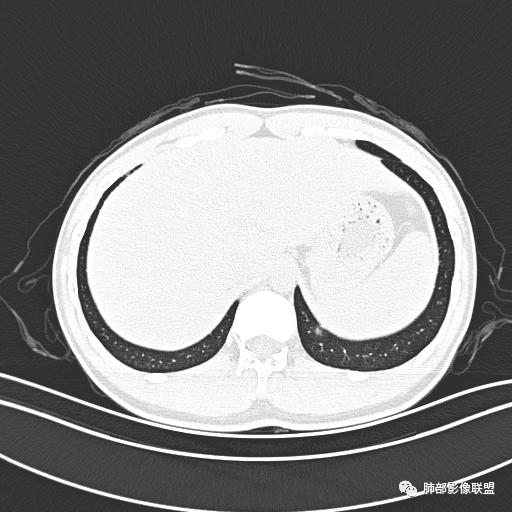

小强:青年,发热,皮疹;双肺散在结节,周围磨玻璃,点晕征,疱疹病毒感染,鉴别荚膜组织胞浆菌,结核。 大雄:青年,急性起病,发热伴全身皮疹2天,抗病毒治疗体温有下降。双肺随机分布大小不等类圆结节,“点晕征”。考虑水痘-疱疹病毒(VZV)血播询问接触史,查体皮疹分布以及形态基本可诊断。 王开金江津中心医院呼吸科:青年男性,起病急,病程短,以发热,皮疹为首发症状,感染指标以单核细胞升高为主,胸部ct双肺多发结界,周围有晕,点晕表现,随机分布,同意於老师意见,水痘疱疹病毒血流感染累及肺。 王秀仙:双肺多发大小不等结节,周围有晕,边缘模糊,呈点晕征表现。青年,急性起病,发热伴全身皮疹2天,抗病毒治疗体温有下降。考虑疱疹病毒。鉴别荚膜组织胞浆菌。 傅昌瑜:19岁男性,发热、全身皮疹2天,单核细胞增高,双肺多发结节,结节边缘见边界不清磨玻璃影。点晕征+发热、全身皮疹+单核细胞增高——考虑水痘-带状疱疹病毒肺炎。 一切∮随缘:年轻男性,发热,皮疹两天,实验室,CRP,PCT增高,影像:双肺多发散在磨玻璃结节,边界欠清,大小不等,呈点晕征改变,以血管束周围分布为主,局部血管束略增粗,其它无明显改变,考虑:1:病毒性肺炎(水痘疱疹病毒?不知道皮肤有无改变)2:真菌(组织胞浆菌,血管侵袭性肺曲霉)3:GPA4:寄生虫(实验室没有看到嗜酸细胞增高) 赵山河:双肺散在结节,周围有晕,边缘模糊,呈点晕征表现。青年,急性起病,发热伴全身皮疹2天,抗病毒治疗体温有下降。考虑水痘—疱疹病毒感染。洪桥爱:青年男性,发热、皮疹2天,伴瘙痒,皮疹于面部首发,之后进展至全身,虽然没有对皮疹进行描述,但是从出疹时间及皮疹进展情况,伴瘙痒,应该就是个水痘患者;CT提示双肺随机分布结节影,部分结节伴有边界不清晕征,考虑水痘血播肺。 刘强:年轻男性,急性起病,皮疹,发热,抗感染治疗体温下降,说明有效。影像表现为散在点晕征,感染类疾病谱(疱疹病毒,真菌,结核),结合年龄,皮肤皮疹,考虑水痘-疱疹病毒性肺炎。 小兜:男性,19岁,发热皮疹两天,颜面部至全身,CRP,降钙素及单核增高。CT示双肺散在小结节,周围伴磨玻璃影,点晕征,考虑为水痘-带状疱疹病毒(varicella-zoster virus,VZV)肺炎 必有路:青年,皮疹+发热+“点晕征”→水痘-疱疹病毒(VZV) 许慧良:青年男性患者,发热、皮疹2天,体温最高38.5℃,第3天皮疹扩展至全身,伴瘙痒,胸部CT:双肺多发随机分布的小结节,结节周边见边界模糊的晕征,考虑水痘病毒感染流心明智:男,19,急性起病,发热伴全身皮疹2天。出疹顺序头→全身,抗病毒有效。胸部CT:两肺多发大小不等类圆形实性小结节影,随机分布,结节周围环绕GGO,边界模糊,呈点晕征。出疹特点是关键,未提示。考虑:血播病毒性肺炎,水痘-疱疹病毒?麻疹?鉴别荚膜组织胞浆菌、TB、血管炎、寄生虫等。 浪迹天涯:病灶多为5-10mm大小结节,结节周围可见磨玻璃样的晕环,常多发,可分布于肺内任何区域,考虑水痘—带状疱疹病肺炎如果短时间内有新的一个区域浸润,更加能说明,